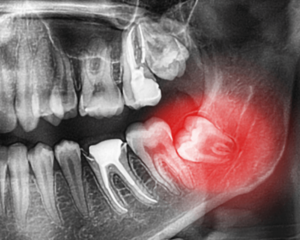

下の親知らずを抜く時のリスク

親知らずって、実は色々な生え方をしているんです。

下の顎に生えている親知らずには3つのタイプがあります。

1)まっすぐ生えている親知らず

2)半分歯茎に埋まっている親知らず

3)完全に歯茎に埋まっている親知らず

完全に歯茎に埋まっている親知らずは、親知らずを覆っている歯茎を切開し、親知らずの周りの骨を削合し、親知らずを抜きやすい形にカットして抜きます。

◆親知らずを抜くときのリスク

抜いたあとに腫れるなどがありますが、最大のリスクは顎の下にある太い神経、下歯槽神経を傷つけることです。

顎の下には下歯槽神経という下の顎周辺の知覚を支配する神経が下顎の骨の中に走行しております。

その神経に親知らずの歯の根が近いことが多々あり抜歯処置をする場合、神経を傷つけるもしくは切断するケースがあります。

神経の損傷がおこると頬から下顎にかけて麻痺が生じる下歯槽神経麻痺が起こることがあります。